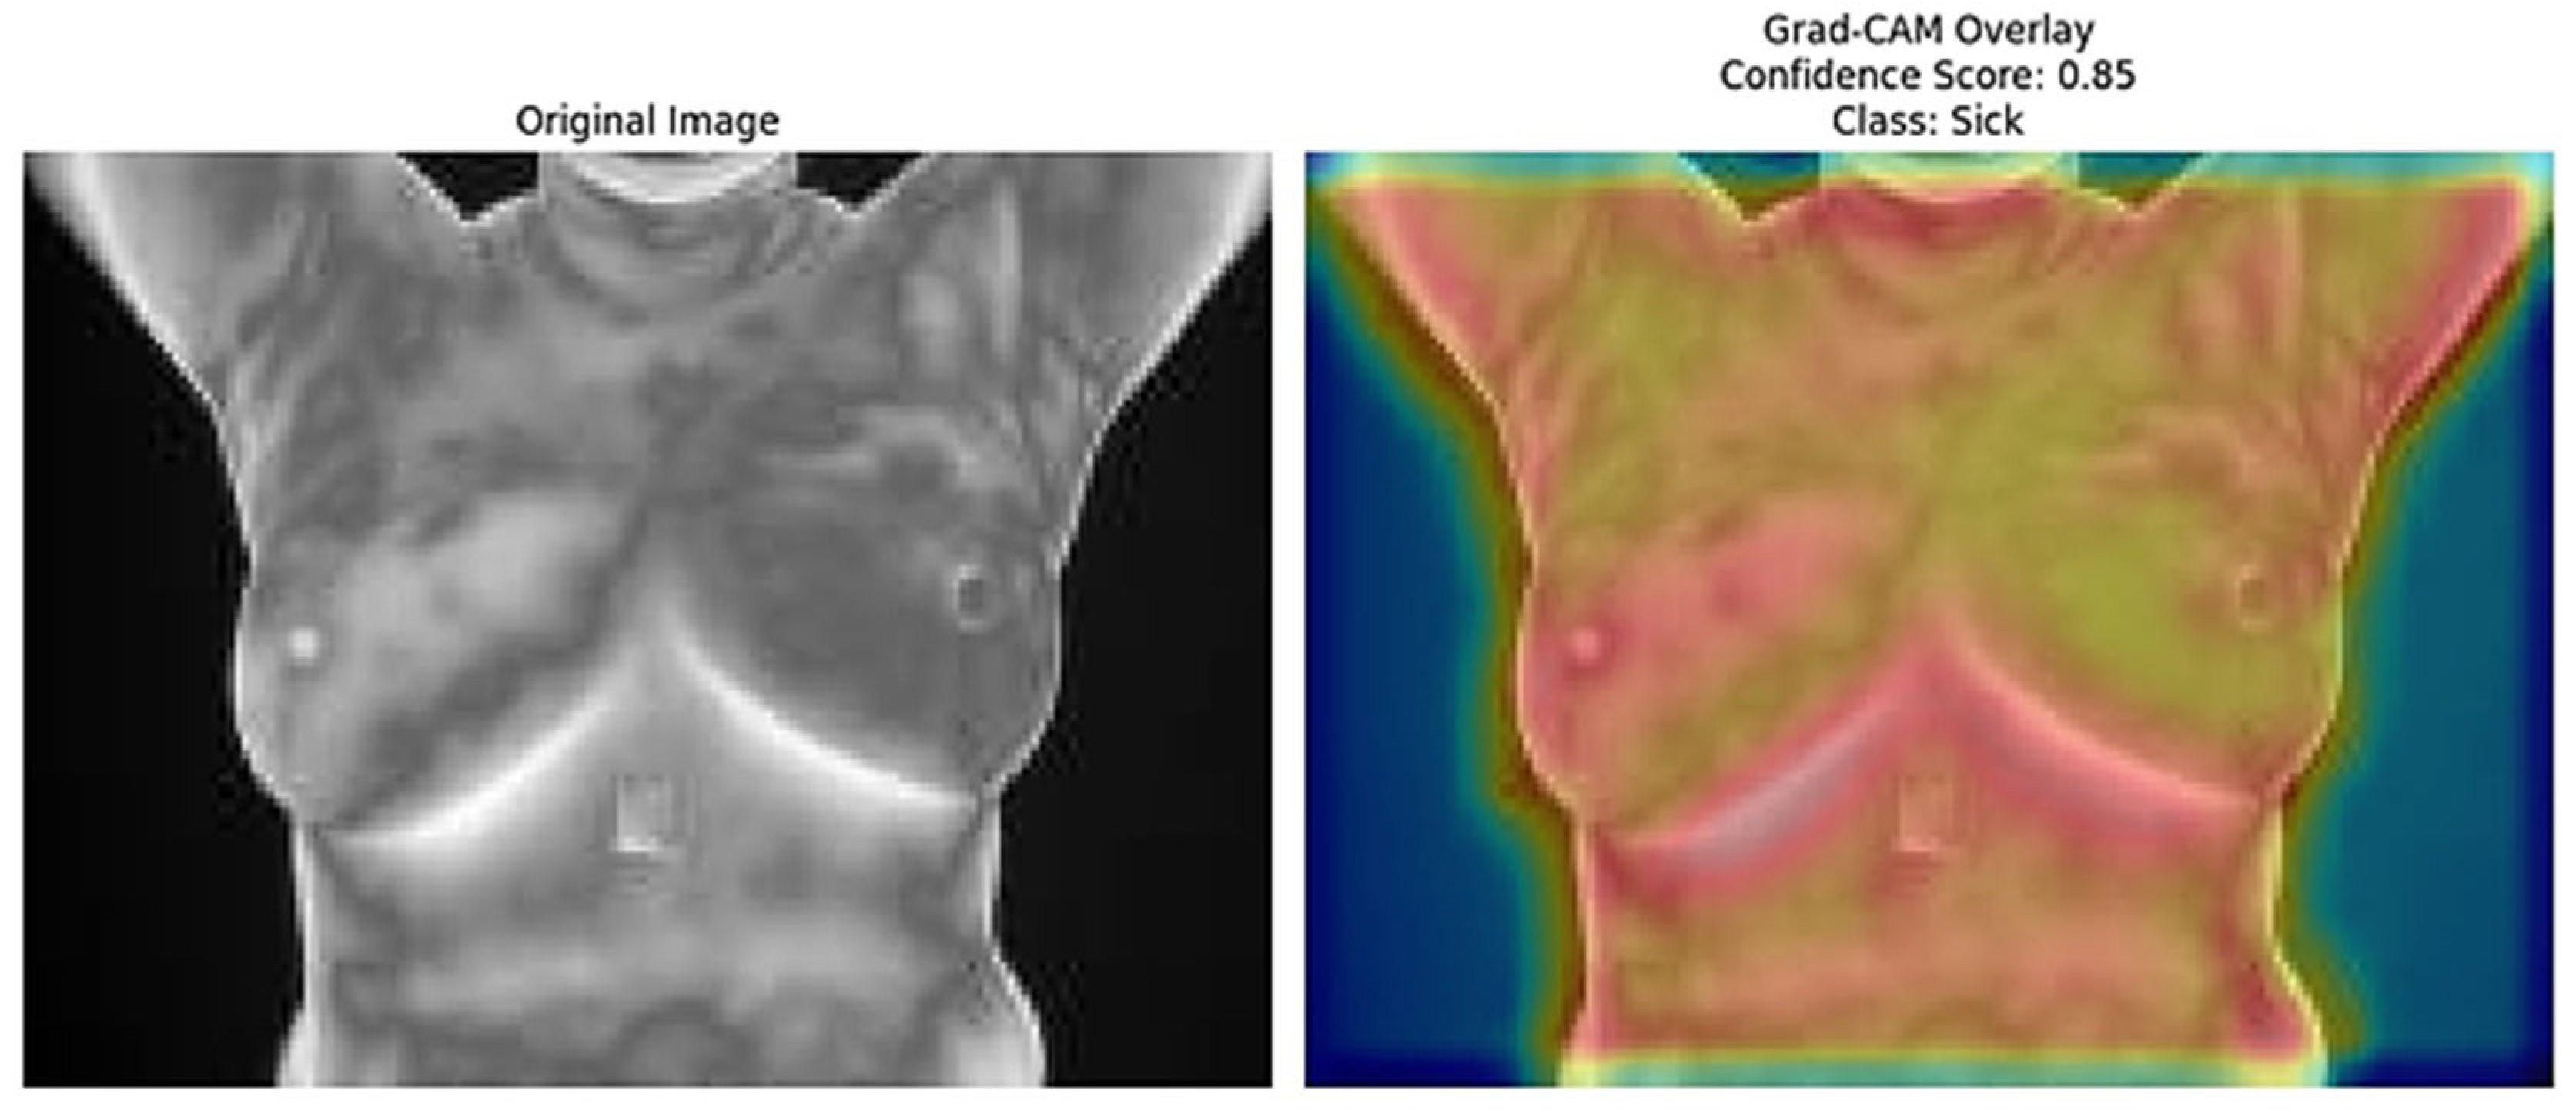

The Grad-CAM [41] overlays provide an essential layer of explainability to the ResNet152 + SVM model by highlighting regions of interest (ROI) that significantly influence the model’s predictions. These heatmaps, specific to each predicted class (e.g., normal, sick, malignant, benign), offer class-specific activation maps, shedding light on how the model differentiates among categories. By incorporating confidence scores (e.g., 0.80, 0.85) alongside these visualizations, clinicians can better understand and trust the model’s decision-making process. This approach directly addresses the “black-box” nature of deep learning models by visually explaining their predictions. Moreover, Grad-CAM overlays emphasize biologically relevant regions, such as abnormal heat patterns [56], as depicted in Figure 15, Figure 16, Figure 17, Figure 18 and Figure 19, enhancing the model’s interpretability and robustness in feature extraction. These insights validate the model’s focus areas against clinical knowledge and bridge the gap between AI-driven predictions and practical clinical applications, paving the way for greater trust and usability in real-world diagnostic settings.